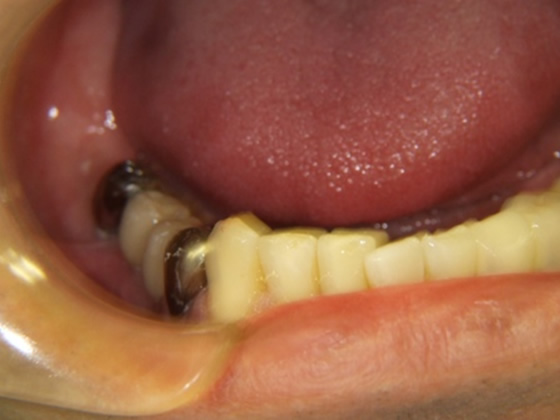

50歳代 男性 右下臼歯部 インプラント植立

インプラントを埋め込んだところ(横から)